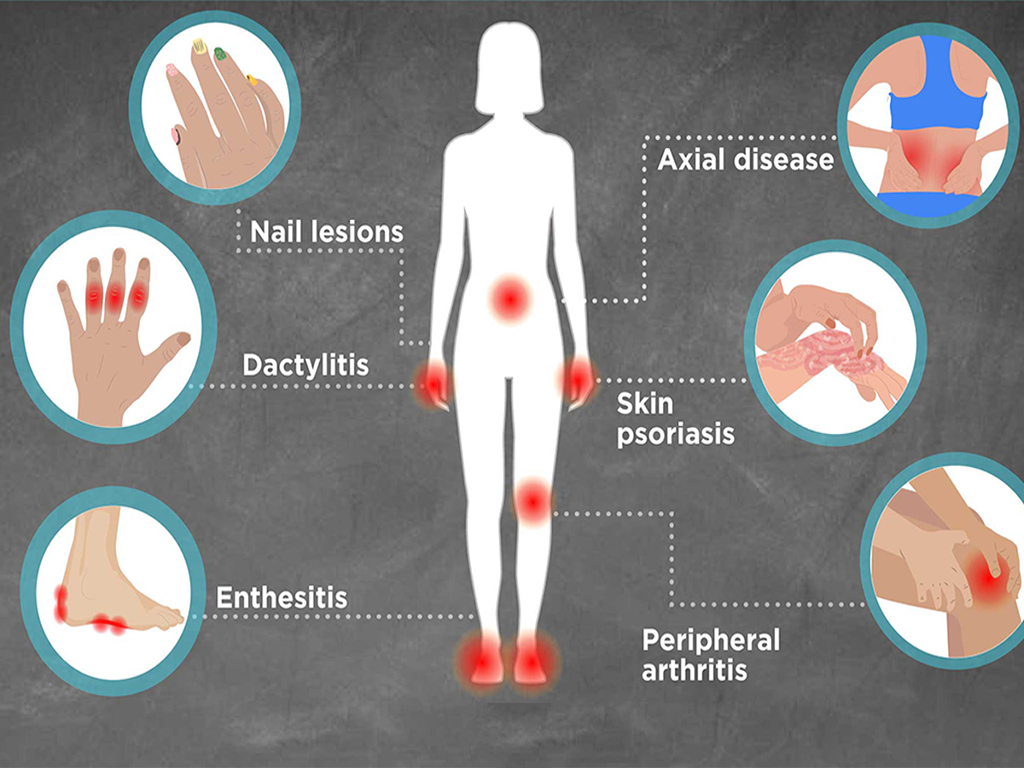

Patients visiting the Best Hospital for Hip Replacement in Gurugram Sector 52 often experience conditions such as osteoarthritis, rheumatoid arthritis, or hip fractures. The goal of the surgery is to relieve pain, restore movement, and improve overall quality of life.

This process includes reviewing the patient’s medical history, performing physical examinations, and conducting diagnostic tests such as X-rays or MRI scans. These assessments help determine the severity of joint damage and the most suitable surgical approach.